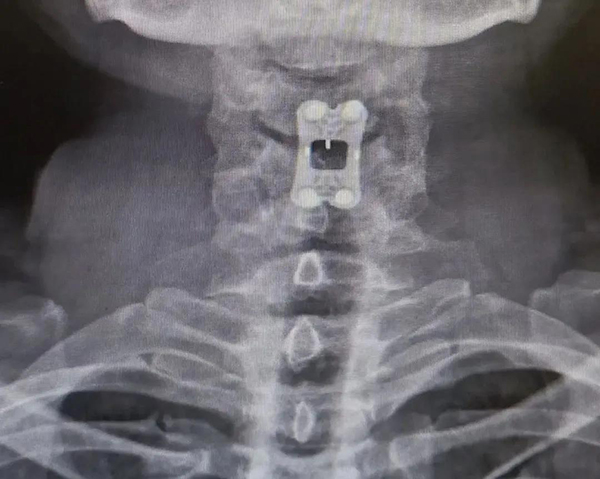

IRENE Anterior Cervical Plate System V helps a patient restore to health

History:Comminuted atlantoaxial fracture with atlantoaxial dislocation

Clinical diagnosis:Comminuted atlantoaxial fracture with atlantoaxial dislocation, central spinal cord syndrome, spinal cervical spondylosis

Treatment:IRENE Anterior Cervical Plate System V

After-op